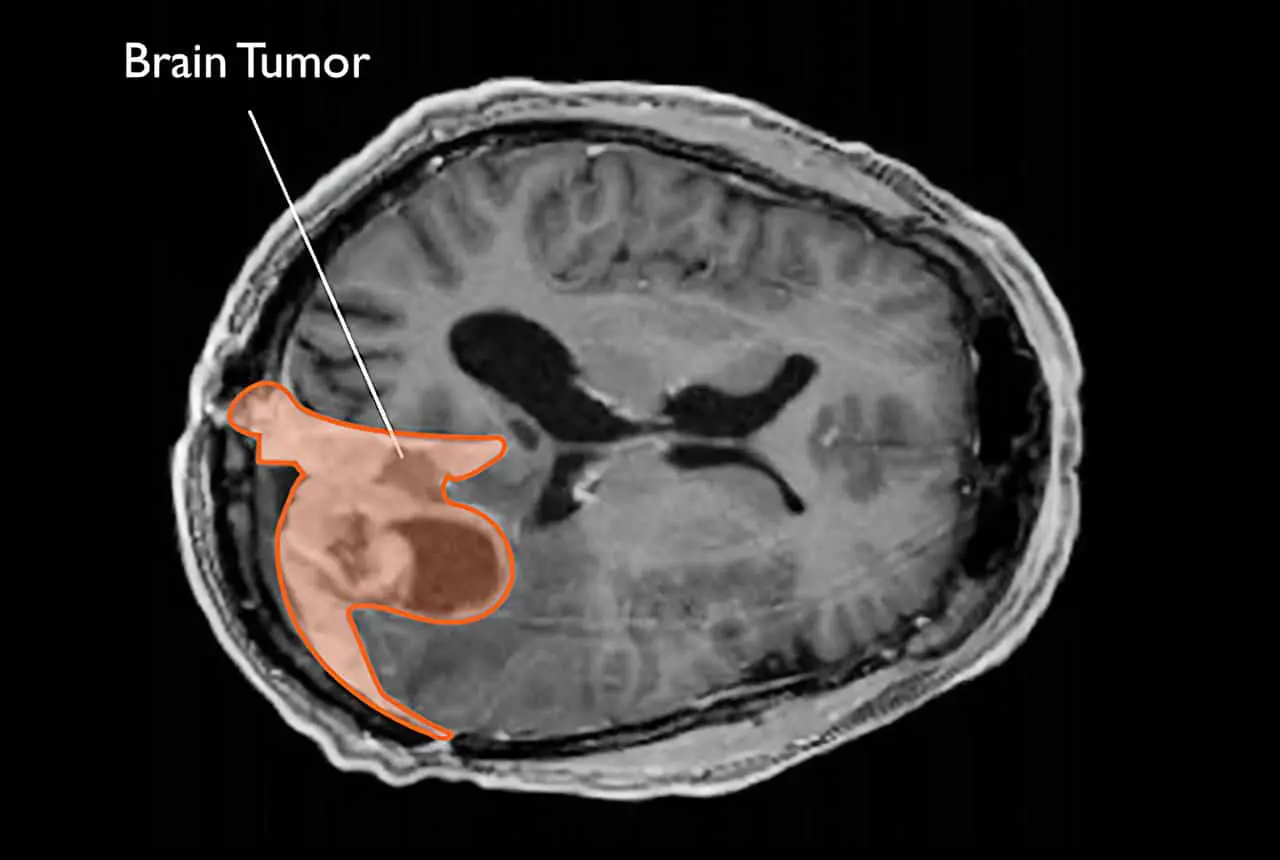

Одним из поводов для дополнительных исследований стали упоминания в зарубежной медицинской литературе о регистрации менингиом у женщин, прошедших длительный курс инъекций депо-медроксипрогестерона ацетата. Менингиома — это распространённая опухоль головного мозга, которая чаще всего имеет доброкачественный характер и хорошо поддаётся хирургическому лечению. Однако существует и небольшая вероятность развития злокачественных форм.

Современная эпидемиология и медицина всё чаще говорят о необходимости сбалансированного принятия решений в вопросах гормональной терапии. Напоминаем, что большинство менингиом доброкачественны и успешно лечатся. Тем не менее, знание своих индивидуальных рисков помогает сделать осознанный выбор и обсудить с врачом оптимальную стратегию ведения репродуктивного здоровья.